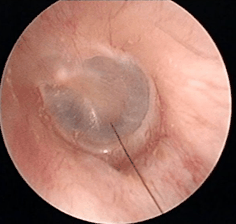

① 请另一个人固定娃的头部和身体;

② 拉直耳道、扩张耳道口。用拇指、中指向后下轻轻拉耳垂,食指向反方向按压;

③ 推开耳屏前皮肤,露出耳道口;

④ 用一支直光远射小电筒(手机闪光灯是不行的),向耳道内垂直照射,这样就能看到耳屎了。

PS:如果看不到,可能是耳道没拉直,或者没选对光源,光是散的;或者,小婴儿耳道绒毛遮挡,这种情况需要电耳镜才能更好的看见。